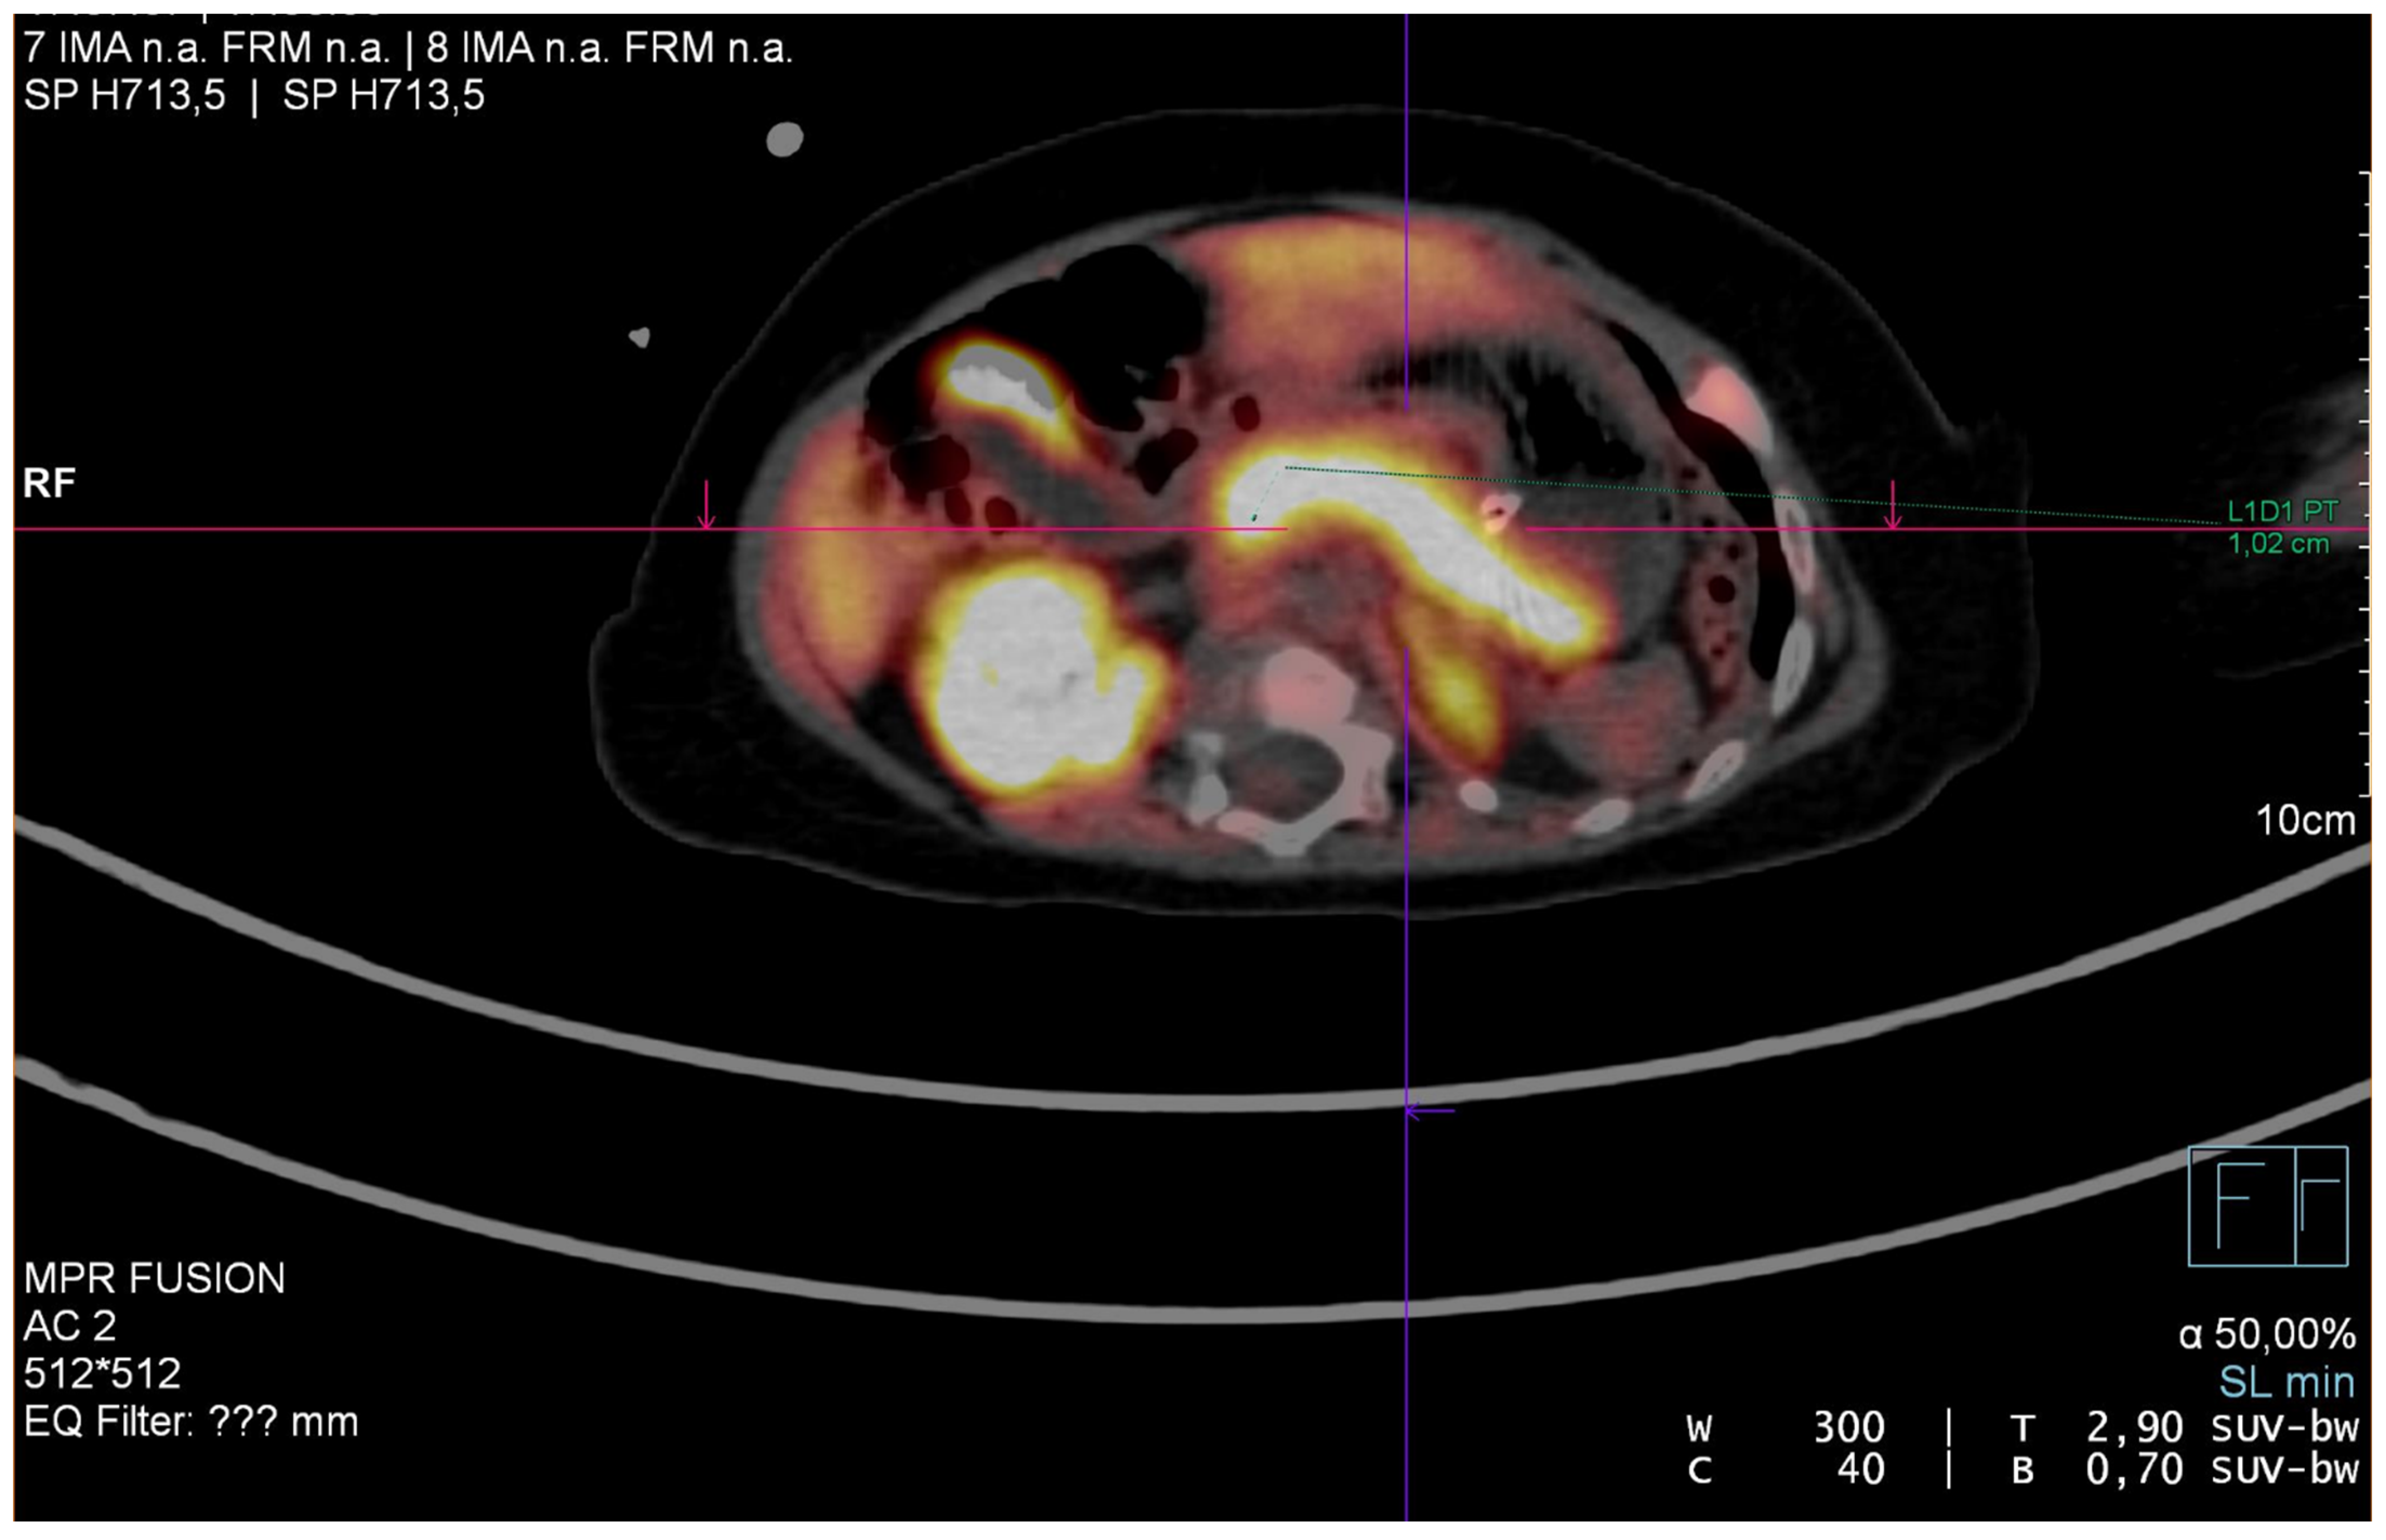

| (18)F-DOPA PET | Fluorine-18-dihydroxyphenyloalanine Positron Emission Tomography |

- Burroni, L.; Palucci, A.; Biscontini, G.; Cherubini, V. Early Diagnosis of Focal Congenital Hyperinsulinism: A Fluorine-18-Labeled l-Dihydroxyphenylalanine Positron Emission Tomography/Computed Tomography Study. World J. Nucl. Med. 2021, 20, 395. [Google Scholar] [CrossRef]